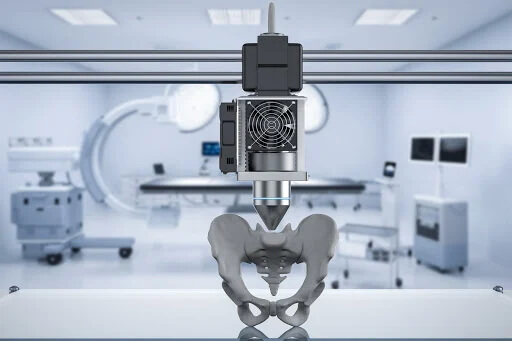

Головна задача у лікування пухлин кісток та суглобів – зберегти функцію кінцівки. Для цього використовують складні індивідуально виготовлені системи для остеосинтезу та ендопротезування, які компенсують втрачені при хірургічному видаленні кісткові тканини.